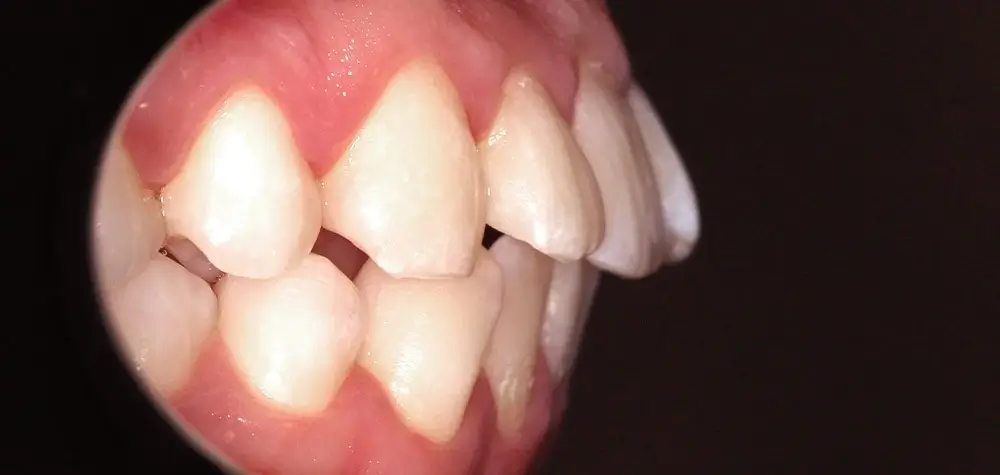

Скученность - Кейс 10

Эффективность устранения дефекта прикуса посредством элайнеров FlexiLigner.

16

Количество кап НЧ

Количество кап ВЧ

Результаты лечения